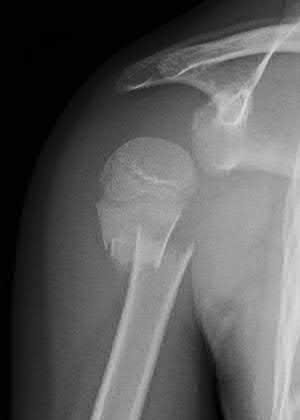

A 55-year-old active female undergoes a primary total hip arthroplasty. The surgeon opts for a ceramic-on-ceramic bearing surface to maximize longevity. Which of the following complications is uniquely associated with this specific bearing couple compared to metal-on-polyethylene?

Options:

Correct Answer: Squeaking

Explanation:

Squeaking is an audible complication unique to hard-on-hard bearings, specifically ceramic-on-ceramic (CoC) total hip arthroplasties. It occurs in up to 10% of CoC THAs and may be related to component malposition, edge loading, or microseparation. Trunnionosis and galvanic corrosion are associated with modular junctions (like a metal head on a metal stem). Pseudotumors are classically linked to metal-on-metal bearings.